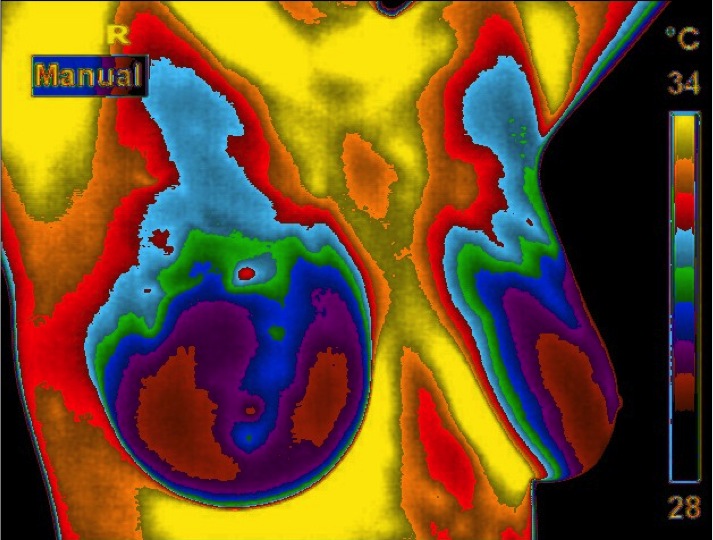

Normal Image  Abnormal Image: Cancer in the left breast

missed by a Mammogram